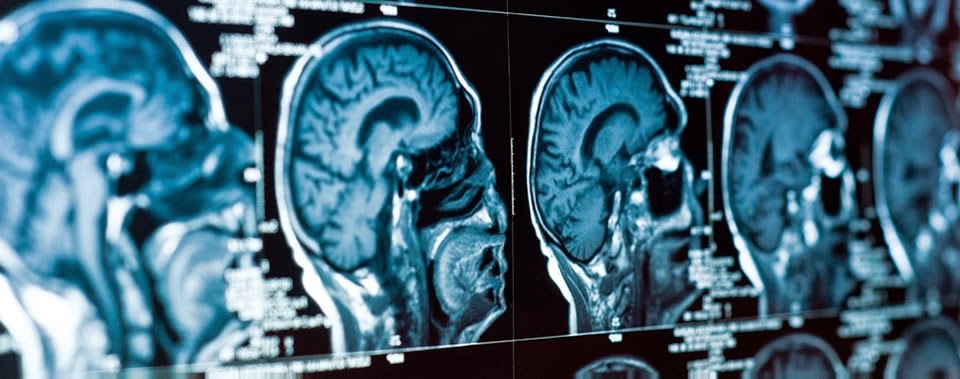

Diagnostic imaging definition. Ultrasound is now widely used as a diagnostic tool. One important diagnostic feature of this condition is a mild rash. The thesis that moral decline. Medical imaging is the technique and process of creating visual representations of the interior of a body for clinical analysis and medical intervention as well as.

Radiologists at main line health use the latest technologies to perform imaging tests quickly accurately and comfortably. 1 diagnostic reference levels in medical imaging. Review and additional advice a web module produced by committee 3 of the international commission on radiological. Imaging definition a technique in which one uses mental images to control bodily processes and thus ease pain or to succeed in some endeavor that one has visualized.